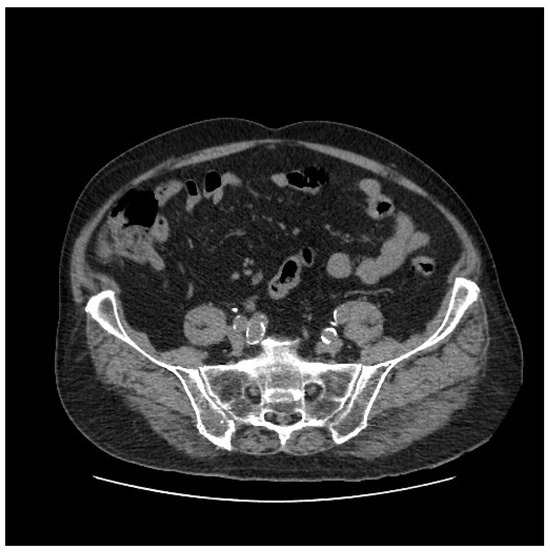

In our case, the presence of IIAA rupture, as indicated by preoperative CT angiography, led to the decision to proceed with an endovascular approach, considering the patient’s fragility. This strategy aimed to fully cover the IIA with an endograft. A review of previous CT scans from one month prior to the rupture event revealed no evidence of aneurysms; instead, only atherosclerosis of both iliac arteries and some ectasia of the right common iliac artery (with a maximum diameter of 18 × 20 mm) were noted, with the IIA measuring 13–15 mm in the portion that was most ectatic. See Figure 4.

Figure 4. Abdominal CT scan performed one month prior to the rupture event showed no evidence of aneurysms.